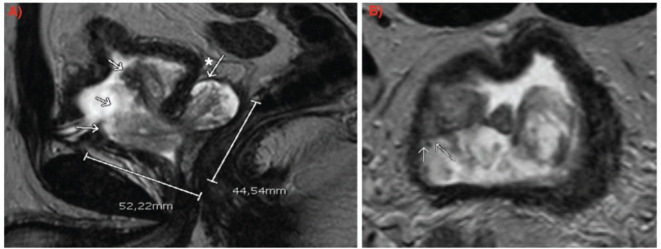

Prostate stromal tumour of uncertain malignant potential is a term used to describe a specialised proliferation of stromal cells within the prostate, most tend to be benign, but some can present with local invasion or progress to prostatic stromal sarcoma with distant metastasis. Fortunately, they represent less than 1% of prostate cancers and only a few cases have been described in the literature. We report a case of a 39-year-old male patient who was referred to our centre with this recent diagnosis in the context of acute urinary retention. After an interdisciplinary consideration, a radical prostatectomy was decided for treatment.